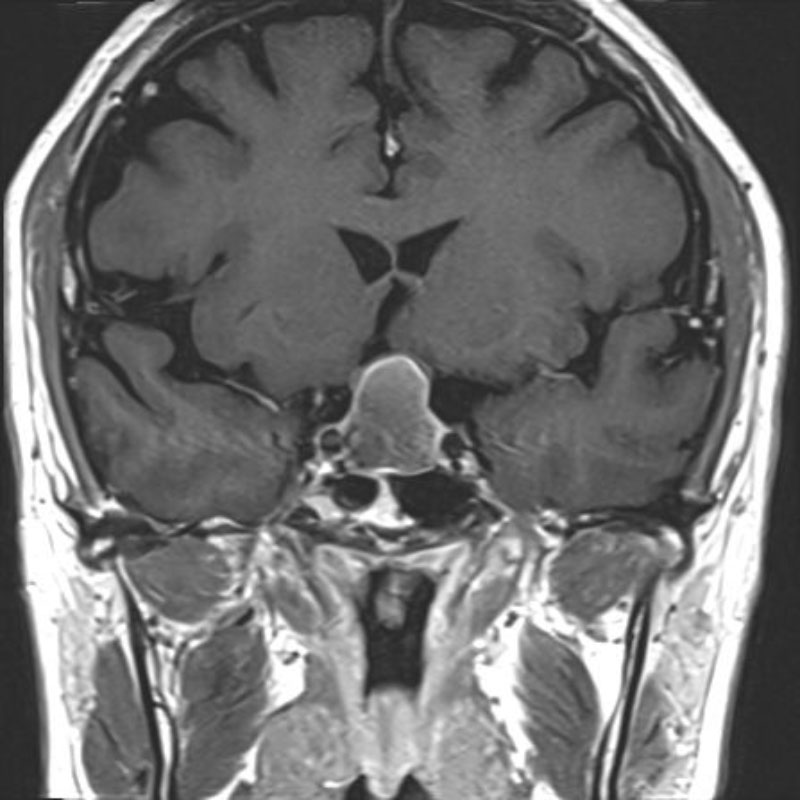

下垂体腺腫

No.’25_102 手術前1

No.’25_102 手術前2